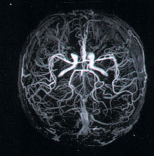

Отклонения в состоянии сосудов, которые сопутствуют ВСД и вызывают дисфункцию мозга видны при МРТ-реконструкции сосудов головы. Сопоставление сосудистых изменений с изменениями в ткани мозга помогает уточнить диагноз вегетососудистой дистонии (ВСД).

Снимки МРТ реконструкции сосудов головы (выше) без применения контраста. Современные методы диагностики сосудистой патологии головного мозга с использованием современного МРТ оборудования.